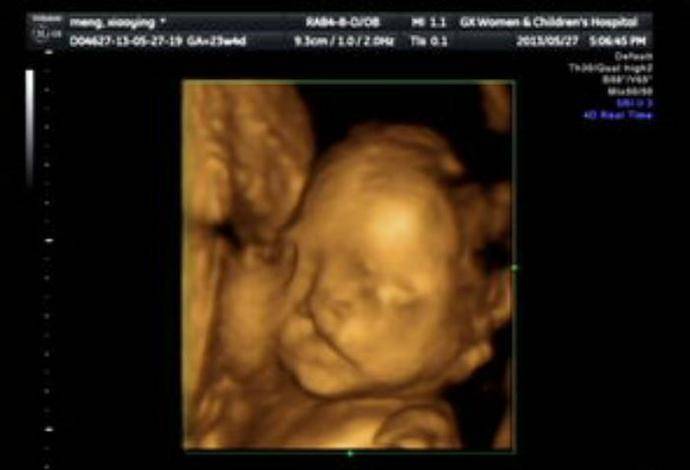

後來,通過超音波檢查,女子發現寶寶似乎個性非常活潑,在肚子裡不停翻身,一下子摸嘴巴,一下子又抓抓耳朵,甚至會摀著臉就像在哭泣一樣,逗得她開心直呼:「孩子會做鬼臉呢!將來一定很聰明!」

然而,站在一旁的醫生看完後,卻皺起眉頭,露出十分擔憂的表情,嘆了一口氣對準爸媽,「還是把孩子流掉吧!」他進一步解釋,「其實孩子看起來在笑,是因為有很嚴重的唇裂,從嘴巴一直裂到了耳朵,而以目前的醫學技術,根本就無法透過手術修復如此大的缺陷,所以還是別留了,生下來對他也是一種折磨。」